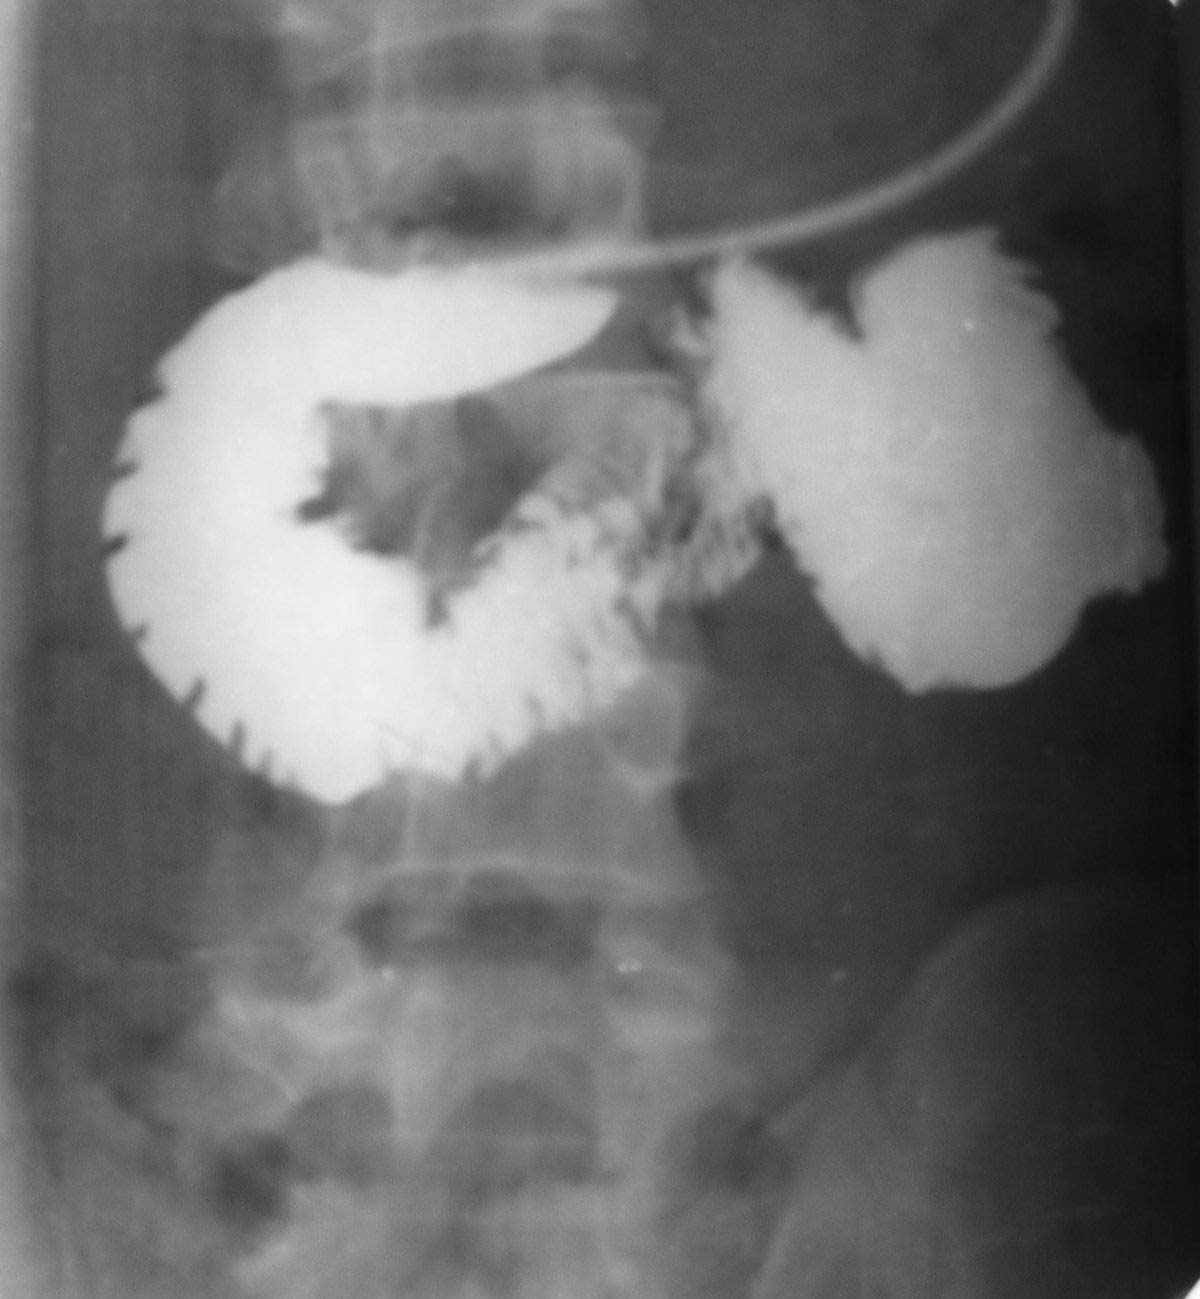

| а – СРВА-2 ("конец в конец"); б – СРВТ; в – СРВА-2 при удвоенной почечной вене; г – СРВА-2 при кольцевидной почечной вене; д – СКВА; е – СКВА + РПВА. Рисунок 6 – Разработанные венозные анастомозы | ||

| Рисунок 7 – Смещаемость ДПК в различных положениях тела | |

При сравнительном анализе смещаемости поджелудочной железы и левой почки, оказалось, что одинаковой она была у пяти (9,3%) из 54 больных, левая почка больше смещалась вниз у 18 (33,3%), поджелудочная железа больше смещалась вниз у 31 (57,4%) больного (рис. 7, стр. 28). Практическое осуществление некоторых межсистемных венозных анастомозов предполагает перевязку вен. Сведения литературы, опыт нашей клиники и проведенные эксперименты свидетельствуют о допустимости перевязки нижней брыжеечной вены и селезеночной вены. При перевязке селезеночной вены включаются коллатеральные пути оттока через желудочно-пищеводные, забрюшинные вены, экстраорганные вены селезенки в систему полых вен, минуя печень. При положительной компрессионной пробе, при создании анастомозов, в 24% случаев можно пережимать левую почечную вену без выключения артериального кровотока в почке. При этом отток крови происходит через гонадную, надпочечниковую вены и поясничные коммуниканты почечной вены.